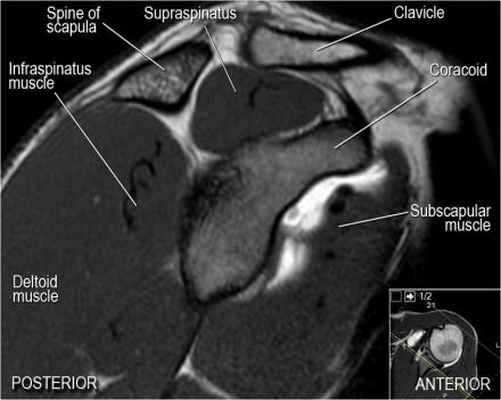

Нормальная корональная анатомия плечевого сустава и контрольный список

- обратите внимание на клюво-ключичную связку (coracoclavicular ligament) и короткую головку двуглавой мышцы (short head of the biceps).

- обратите внимание на клювоакромиальную связку (coracoacromial ligament).

- обратите внимание на надлопаточный нерв и сосуды (suprascapular nerve and vessels)

- поищите импинджмент надостной мышцы за счет остеофитов в акромиально ключичном суставе или из-за утолщения клювовидноакромиальной связки.

Нормальная сагиттальная анатомия и контрольный список

- обратите внимание на мышцы манжеты вращателей и поищите их атрофию

- обратите внимание на форму акромиона